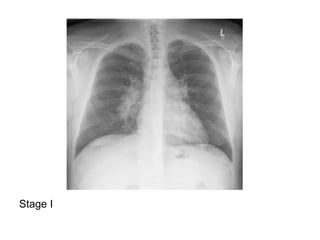

Stage 0 : normal chest radiograph

Stage I : hilar or mediastinal nodal enlargement

Stage I